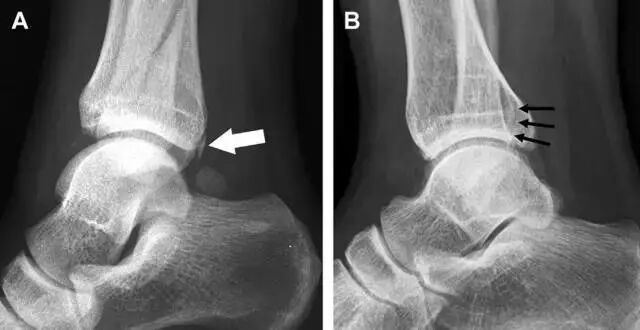

胫骨后踝骨折

涉及到三角韧带和外侧副韧带(LCL)的复杂性骨折常常不难发现,尤其是存在表面软组织肿胀时。然而,后胫腓韧带牵拉引起的胫骨后踝骨折则很难发现。这些骨折大小不一(图 2),却很重要,因为他们常与胫骨远端螺旋骨折有关,或者是三踝骨折的一部分。

图 2 胫骨后踝骨折。A 侧位片示来源于胫骨后踝的一个小骨折碎片(箭头),因踝部扭伤导致;B 另一位跖屈损伤的患者,侧位片示一个大骨折块(箭头)